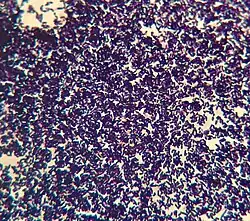

Gram staining allows for visualization of the bacteria's cell wall composition based on the color the bacteria stains after a series of staining and decolorization steps.[5] This staining process allows for the identification of gram-negative and gram positive bacteria. Gram-negative bacteria will stain a pink color due to the thin layer of peptidoglycan. If a bacteria stains purple, due to the thick layer of peptidoglycan, the bacteria is a gram-positive bacteria.[5]